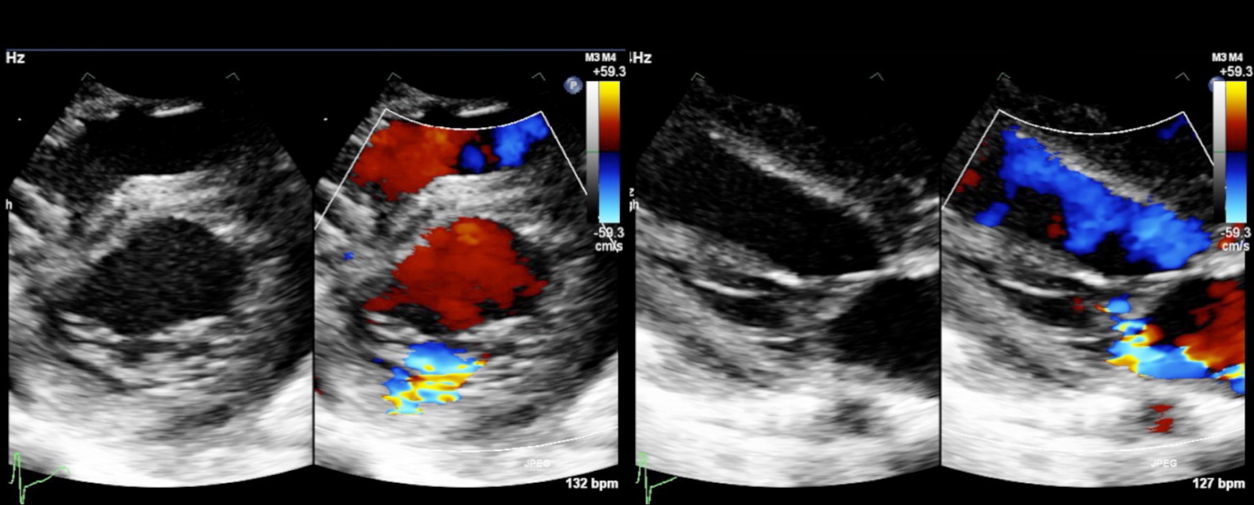

心臓超音波検査

肺動脈弁下部型VSDとP2を中心とした後尖低形成によるmoderate MRを認めた.僧帽弁輪径は17.3 mm(117% of normal)であった(Fig. 5).

Pediatric Cardiology and Cardiac Surgery 35(1): 52-58 (2019)

Fig. 5 Preoperative echocardiogram of case 2

Moderate mitral valve regurgitation is shown. Posterior mitral leaflet, especially middle part (P2), is hypoplastic.